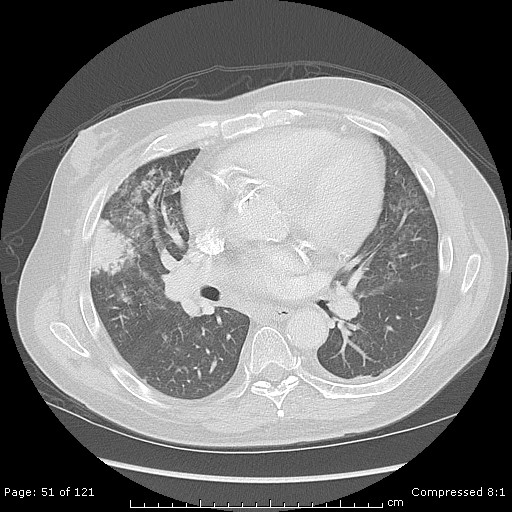

In this patient, bronchoscopy with BAL, brushing, and trans-bronchial lung biopsy were performed. Cultures including bacterial, viral, and fungal were negative. Legionella, nocardia, AFB and pneumocystis were negative as well. Cytology examination of the BAL and bronchial brush samples revealed no evidence of malignancy. Transbronchial biopsies were taken and these also did not show malignant cells. Pathologic examination of the transbronchial biopsies revealed normal alveolar structures with crush artifact, mildly atypical cells, and submucosal calcifications. Specimens stained for AFB and fungus were negative as well.

Trans-thoracic needled aspiration (TTNA) has become a well-established and widely utilized procedure for the diagnosis of peripheral lung nodules. A recent study has demonstrated a sensitivity of 92% and 100% in malignant and benign disease, respectively5. Although there the sensitivity for diagnosis of both benign and malignant disease is high, there are certainly associated complications from CT-guided TTNA. Severe complications such as hemorrhage (1%), pneumothorax (15%) and pneumothorax requiring a chest tube (6.6%) are reported6. In this case, the fact remains that this dense, consolidated, peripheral pulmonary nodule persisted over many weeks despite antibiotic therapy. Furthermore, there was no evidence for spread to other organs or the mediastinum. At this point, referral for surgical lung biopsy is warranted, making answer choice D correct.

The pathology from the right middle lobe wedge resection is consistent with pulmonary calcinosis. The biopsy shows dystrophic calcifications of the lung interstitium and blood vessels. The term dystrophic refers to calcium deposition in previously injury tissue, as opposed to metastatic calcification, which occurs in non-injured tissue.

Pulmonary infarcts are typically wedge-shaped, peripheral pulmonary lesions with the broad base abutting the pleural surface as was seen with our patient. Histopathologically, pulmonary infarction is characterized by basophilic necrosis. Granulomatous changes have been noted as well13.The majority of specimens have vascular inflammation, however calcification in the lung parenchyma and vasculature has not been reported, making answer choice B incorrect.